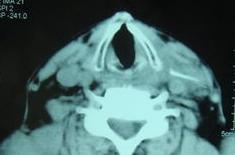

查体 : 心肺 ( - ), 神经系统未见异常, 右胸锁乳突肌中1/3 处自 其 后缘向 后下方 有一长 约3. 5 cm× 0. 3 cm条状硬包块 , 其上端表浅 , 位于皮下 ; 下端较深 ,且有压痛 , 质硬、活动度较好, 咽喉腔粘膜无充血及糜烂、 窦道 辅助检查:颈部B超、X线提示异物。血尿常规、肝肾功等无明显异常。

随访:门诊随访1年半, 无疼痛及异物感等表现 。 讨论:咽及食道异物为常见病 , 但异物穿透咽 、食道 壁至腔外者少见, 称迁徙性咽食 道异物 , 亦称咽食道腔 外异物 , 常易误诊 、漏诊。若异物较深, 治疗不及时 , 或刺伤重要器官,可 造成致命的危险。迁徙性异物在体内 迁 移的程度及远近 , 常与异物的形状 、 肌肉的挤压等因素 有关, 如锋利针尖状异物 、鱼刺等 , 在内则易于迁移 , 多见于老年患者。患者误吞鱼刺等异物后, 往往吞菜饭团, 试图咽入胃内 , 结 果导致 腔壁 损伤 , 异物迁移; 异物本身引起局部感染 或脓肿形成 , 亦可促异物穿透腔壁迁移它处。迁徙性异物诊断较困难, 应详细询问病史。 该患者多有异物史, 有吞咽进食后疼痛、发 热及痰中带血史 , 怀疑者需做X线片及CT等进一步辅助检查 。迁徙性 异物一 旦确诊, 应及时取出 摘自第三军医大学学报